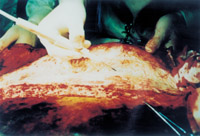

3-5 這是皮膚及皮下組織被切除后的創(chuàng)面情況,表現(xiàn)為深筋膜存在的肌肉層創(chuàng)面

3-6 處理結(jié)果:燒傷皮膚及未燒傷的皮下組織均被切除,胸部燒傷創(chuàng)面變成人為的外科手術(shù)切除的肌肉層創(chuàng)傷創(chuàng)面,已無任何燒傷組織及皮膚組織。